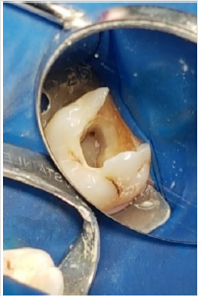

Patient M.A.R., female, 27 years old, went to Endodontic Specialization to treat the first right maxillary molar. The emergency treatment was done in a health Center one month ago. Radiography was performed (Figure 3) and the clinical examination verified the permanence of the fistula (Figure 4). After endodontic access and irrigation with 2.5% sodium hypochlorite (Iodontosul, Porto Alegre, Brazil), the MB2 was localized with # 10 C pilot file (VDW, Munich, Germany) (Figures 5 & 6). Root canal system exploration and electronic working length were performed (Romiapex A-15, Romidan Ltd, Kiryat Ono, Israel). After Glide Path with Proglider was done (Dentisply-Maillefer, Switzerland) and preparation of all channels with Wave One Gold Primary (Dentisply-Maillefer, Switzerland) (Figure 7) The smear layer was removed and calcium hydroxide intracanal medication was done (SS WHITE, Rio de Janeiro, Brazil) and glass ionomer sealing (SS WHITE, Rio de Janeiro, Brazil) were placed. .Patient returns after 40 days, and on clinical examination, fistula regression is observed (Figure 4). In the second appointment, the MB1, MB2 and distal root were enlarged with Wave One Gold Medium ( Dentisply-Maillefer, Suiça) and palatine root has been expanded with Wave One Gold Large (Dentisply-Maillefer, Switzerland), smear layer was removed and obturation performed (Figures 8 & 9).

Figure 3: Initial radiograph showing the emergency treatment done in the health center one month ago.